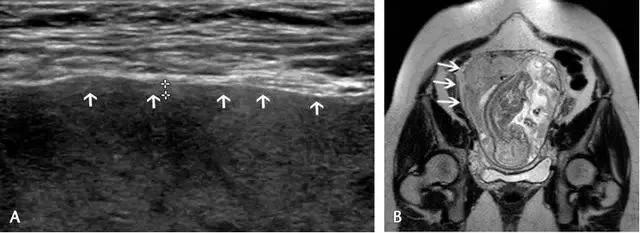

胎盘早剥指胎盘尚未成熟即与子宫壁分离开来的状况,是晚期妊娠出血的主要原因。胎盘前早剥发生于胎盘与羊水之间的绒毛膜板下,较其它类型的早剥少见;胎盘后血肿继发于蜕膜小动脉的破裂,导致血液在胎盘基底板与子宫壁之间积聚,可造成胎盘基底板坏死及绒毛梗死,导致严重不良妊娠结局。

胎盘后复合体通常厚约 1~2 mm,由子宫胎盘血管及肌层所构成;如果超声发现此处增厚,应疑及胎盘后血肿。急性期的血肿回声较胎盘回增强或与之相同,一周后变为低回声,两周后可变为无回声(图 14)。

图 14 示胎盘早剥:A 为孕 24 周时的胎盘横切面,胎盘表面(长箭头)与羊膜(短箭头)之间可见一个较大的低回声区,此为胎盘前早剥。B 为孕 11 周的子宫矢状面,可见胎盘后的慢性无回声出血灶(长箭头),并延伸至绒毛下空间(短箭头),星号示出血灶导致胎盘边缘抬起。C 为另一孕 27 周伴无痛性阴道出血患者的子宫矢状面及横切面,长、短箭头所指回声为胎盘后的亚急性出血灶

超声对于急性或超急性胎盘早剥的检出并不敏感,尤其当出血灶局限于胎盘后方,此时胎盘外膜完整、出血灶处于隐蔽状态。胎盘后出血常常预示胎儿出生后的状况差,因而应积极处理这种出血。